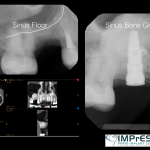

Sinus Augmentation (Sinus Floor Elevation)

Sinus Lift Surgery

Sinus Lift Implant Vancouver Burnaby Periodontist Implant Dentist IMPreESS Perio

Dental Implant Centre in Vancouver Burnaby Sinus Lift Dental implant Surgery Dr. Noroozi Implant Specialist IMPrESS Perio Implant Center.001

Dr. Noroozi Sinus Lift Surgery For Dental Implants IMPrESS Perio Implant Center

Sinus Lift, Bone Graft, Implants Dr. Noroozi IMPrESS Perio Implant Center